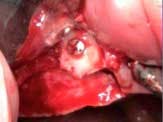

Case 2: Lateral wall sinus osteotomy with block grafting and platelet-rich fibrin (PRF)

Various treatment options were explained to the patient, and a treatment plan consisting of Coldwell-Luc external sinus lift with bilateral block placement in area 5 to 7 and 10 to 12 was agreed upon.

Under local anesthesia, a full thickness flap was elevated from the upper right to upper left posterior segments. Using a piezoelectric handpiece, a buccal window hinge osteotomy was elevated in the maxillary right posterior region. A mixture of DFDBA, anorganic bovine bone, and PRF was placed. A collagen membrane was used to cover the buccal window. Simultaneously, two puros J-block allografts were secured in the 5 to 7 and 10 to 12 region with stainless steel screws (1.6 x 8 mm screws). A mixture of DFDBA, anorganic bovine bone and PRF was placed over each area and covered with PRF sheet and a collagen membrane. Primary closure was obtained with CV-5 Goretex sutures. Healing was uneventful. After six months of healing, six straight implants were placed in sites 3, 4, 5, 6, 11, and 12. Healing abutments were placed at stage I. Healing was uneventful. After four months of healing, six custom abutments were fabricated by his dentist and cover screws were placed on implants 8 and 9 and converted into pontics.